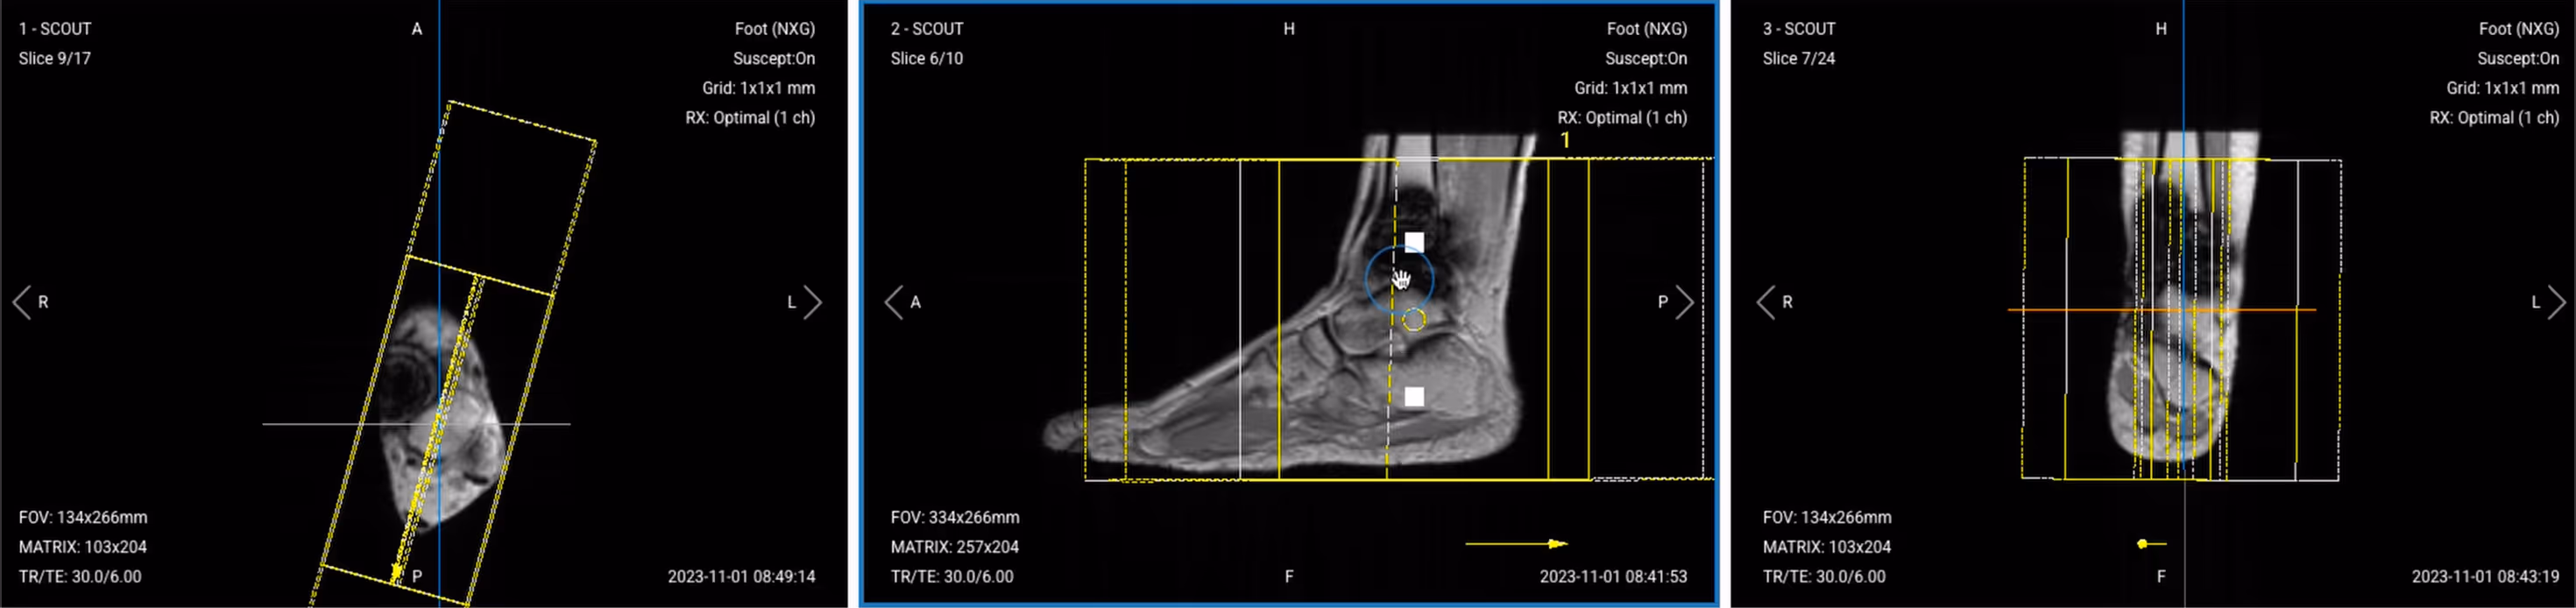

4. Capture the Initial Localizer Images

Before we can perform any MRI protocol, we must always capture initial localizer images of the patient. These images act as a guide for planning the detailed scans we will perform next.

We should always capture localizers in three planes:

1. Axial

2. Sagittal

3. Coronal

Once acquired, upload the initial localizer images into the three viewports.

Then, scroll through each of the image stacks to locate a central slice that clearly shows the anatomy of the ankle.

Correct Setup of Localizer Images for Ankle MRI:

Correct Setup of Localizer Images for Ankle MRI